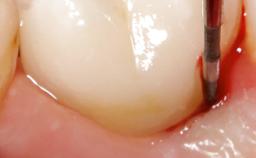

A 70-year-old female patient was referred by her general dentist to the periodontist for assessment and management of an infection associated with implant 36. The general dentist had noted suppuration on probing during examination.